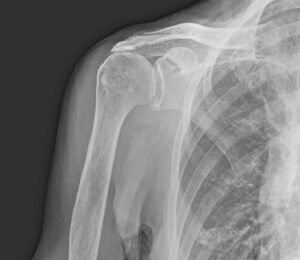

人工肩関節置換術 70代女性

70代女性の右変形性肩関節症に対し、人工肩関節置換術を行いました。

70代の女性の変形が進んだ肩関節です。

上腕骨骨頭と肩甲骨の軟骨の消失により、骨が接触して痛みが生じます。